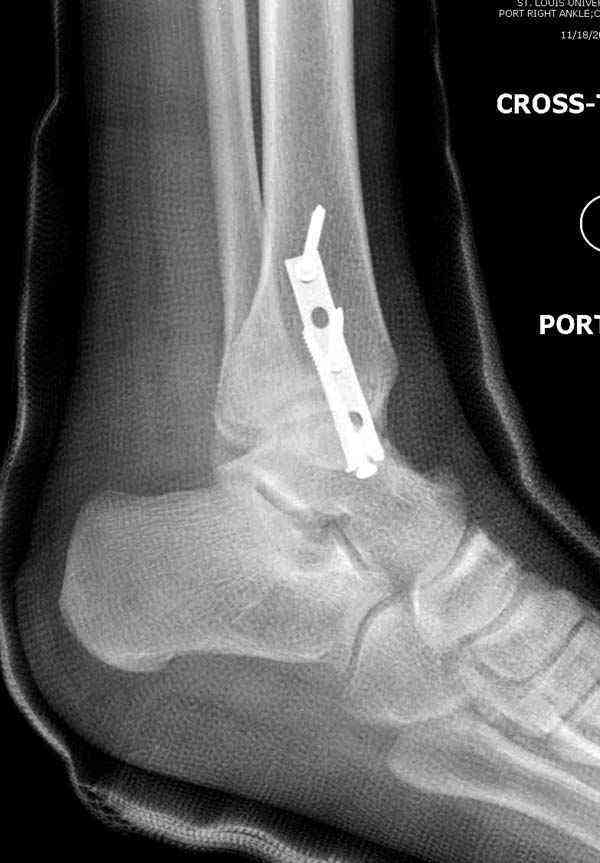

Достаточно быстрое восстановление функции.В октябре 2009г-почувствовала боль,в области рубца над гайкой открылся свищ.На Р-граммах-консолидация переломов и смещение гайки по стяжке.10.11.2009г-конструкции удалены,санация,заживление ран.В настоящее время пациентку ничего не беспокоит.На операции-раскручивание гайки-болталась на конце стяжки.Вопросы:какой механизм раскручивания и что я неправильно сделал?Свои версии:1)в области синдесмоза успела образоваться рубцовая ткань,которая при движении в суставе"пружинила",поскольку голеностопный сустав является спиральным, то и биомеханика подобна кривошипному механизму.2)Реконструктивная пластина не "реконструировалась" по форме лодыжки.Наложил,как есть.То есть подпружинивала сама пластина.Ну,это мои догадки.Что нужно,чтобы избегать впредь таких,пусть и не "страшных"осложнений:Рассверливать через лодыжку область синдесмоза?Ставить шайбу-гровер?Тщательно моделировать пластину?Прилагаю сравнительные снимки-сразу после операции и перед удалением конструкции.

Создаётся впечатление,что болт-стяжка не раскрутился, он не дотянут изначально, и просто мигрировал с течением времени, под действием циклических нагрузок, в латеральную сторону, образовал пролежень и перфорировал кожу. И подвывих не до конца установленным болтом-стяжкой устранён не полностью. Это, что можно сказать по представленным снимкам. А пластину особенно в этой локализации всё таки необходимо моделировать особенно тщательно, я вообще зачастую устанавливаю её по задней поверхности, естественно с моделированием.

Визуально никаких вопросов по репозиции не было.Да и на основании чего сомнения,что наружная лодыжка не полностью репонирована или прорезалась проволка ???Я не вижу...Снимок после репозиции справа.

Нет первичных снимков, перелом очень низкий и под большим сомнением диагноз разрыва синдесмоза. Медиальная сторона отрепонирована на "хорошо" и, по-видимому, прорезание проволоки произошло во время операции. Без снимков трудно судить о высоте малоберцовой, а лодыжка находится в варусе. Лагирование получилось, но возле тонких шурупов передне-задний шуруп выглядит немного тяжеловато.